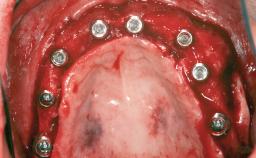

# of Implants 14

Type of Implants Two-Piece

Defining Characteristics Fully edentulous upper jaw to be rehabilitated with four or more implants

Modality Fixed hybrid bridge on 5+ implants